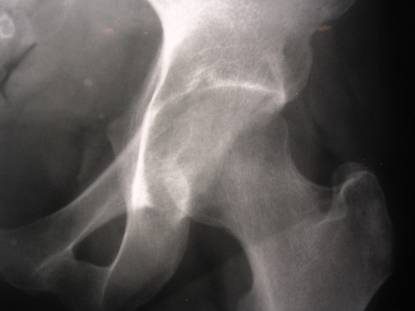

Left hip pain